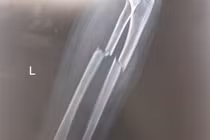

Bé trai 7 tuổi gãy xương cẳng tay, suýt mất vận động sau cú ngã xe đạp

Gãy kín hai xương cẳng tay có di lệch, nguy cơ biến dạng, hạn chế vận động. Phẫu thuật kết hợp xương giúp khôi phục vận động, tránh biến chứng cứng khớp.

Bệnh viện Đa khoa Hồng Ngọc vừa phẫu thuật thành công ca kết hợp xương cho bé trai 7 tuổi bị gãy kín 1/3 trên hai xương cẳng tay trái, có di lệch. Sau mổ, bệnh nhi đã có thể vận động nhẹ nhàng, tập phục hồi chức năng lấy lại vận động.

Gãy kín hai xương cẳng tay có di lệch, nguy cơ biến dạng, hạn chế vận động